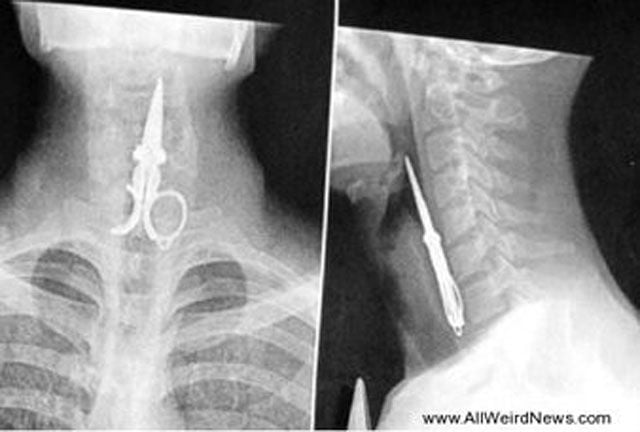

This guy was picking his teeth with a pair of scissors and then started laughing and down go the scissors. He lived and is fine!

X-ray of scissors left inside Pat Skinner's stomach of Hurstvlle during a operation at St George Hospital, Sydney